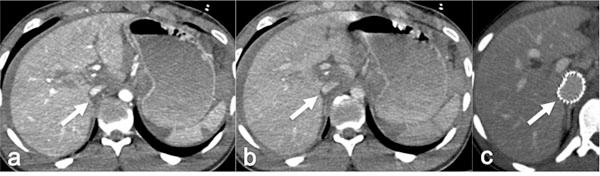

Acute vascular emergencies can arise from direct traumatic injury to the vessel or be spontaneous (non-traumatic).The vascular injuries can also be divided into two categories: arteial injury and venous injury.Most of them are life-treatening emergencies, sice they may cause an important ipovolemic shock or severe ischemia in their end organ and require prompt diagnosis and treatment.In the different clinical scenarios, the correct diagnostic approach to vascular injuries isn't firmly established and advantages of one imaging technique over the other are not obvious.Ultrasound (US) is an easy accessible, safe and non-invasive diagnostic modality but Computed Tomography (CT) with multiphasic imaging study is an accurate modality to evaluate the abdominal vascular injuries therefore can be considered the primary imaging modality in vascular emergencies.The aim of this review article is to illustrate the different imaging options for the diagnosis of abdominal vascular emergencies, including traumatic and non traumatic vessel injuries, focusing of US and CT modalities.

急性血管急症可由血管直接外伤引起,也可为自发性(非外伤性)。血管损伤也可分为两类:动脉损伤和静脉损伤。它们大多是危及生命的急症,因为它们可能导致重要的低血容量性休克或其终末器官的严重缺血,需要及时诊断和治疗。在不同的临床情况下,针对血管损伤的正确诊断方法尚未完全确立,一种成像技术相对于另一种成像技术的优势并不明显。超声(US)是一种易于获得、安全且无创的诊断方式,但多期成像研究的计算机断层扫描(CT)是评估腹部血管损伤的准确方式,因此可被视为血管急症的主要成像方式。本文综述的目的是阐述用于诊断腹部血管急症的不同成像选择,包括外伤性和非外伤性血管损伤,重点介绍超声和CT方式。